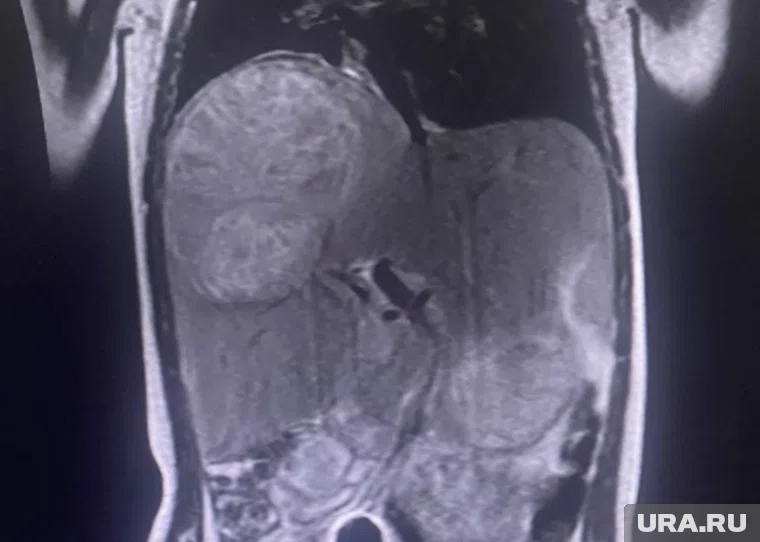

Фото: Министерство здравоохранения Челябинской области © URA.RU

«Хирурги диагностировали у пациента сложный многокамерный абсцесс правой доли печени размером до 12 сантиметров, который затрагивал сразу три сегмента органа. Единственным способом помочь ребенку было удалить правую долю печени вместе с частью диафрагмы: пункция не помогла бы из-за структуры абсцесса», — сообщила пресс-служба ведомства в telegram-канале.